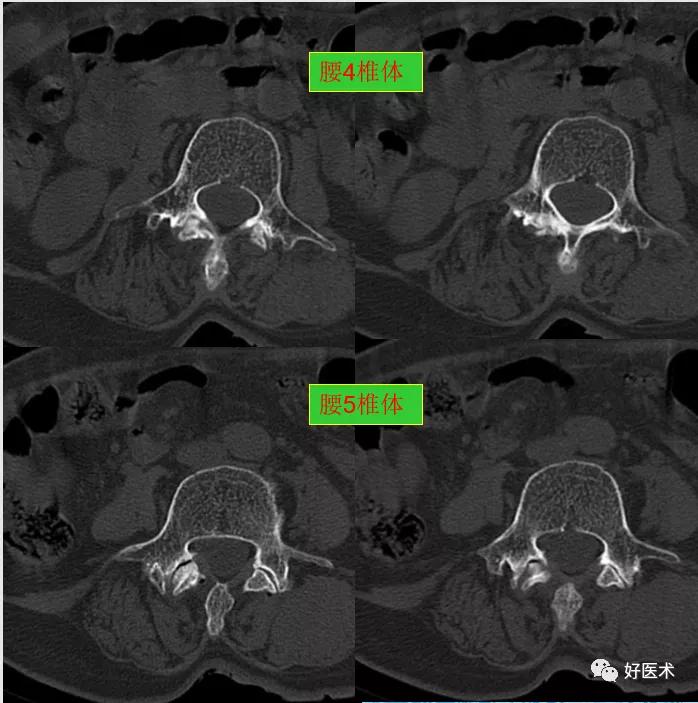

CT图像,腰椎常规采用序列扫描,腰椎体2层,腰间盘4层,层厚2.5mm,一般扫描范围包括腰2--骶1椎体及所属间盘。

腰4、5椎体及附件骨质未见著变。

发现了什么?左侧竖脊肌较右侧明显肿胀饱满, 肌间脂肪间隙消失!!